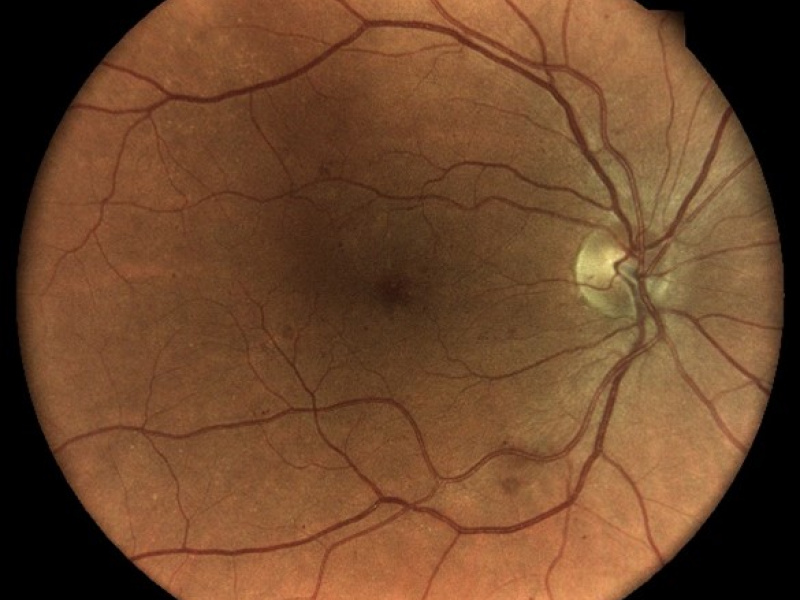

Technologie TrueColor Confocal společnosti iCare překonává limity běžných zařízení pro zobrazování fundu a SLO (scanning laser ophthalmoscop) tím, že kombinuje nejlepší výhody obou. Jednoduše řečeno, fundus kamery poskytují vysokou barevnou věrnost a SLO systémy vytvářejí vysokou ostrost, jasnost, celkovou přesnost a detailnost snímků. Když se tyto vlastnosti zkombinují, vznikne špičkový obraz sítnicové krajiny ve věrných barvách.

Pro diagnostiku a sledování běžných patologií, jako je diabetická retinopatie, musí být zařízení pro zobrazování očního pozadí schopna kombinovat vysoké rozlišení, vysoký kontrast a vysokou barevnou věrnost. To umožňuje zachytit drobné rysy a detaily a rozlišit jednotlivé změny, které byste jinak mohli snadno přehlédnout. Zatímco standardní systémy SLO mají vysokou jasnost, ostrost a kontrast, tradiční fundus kamery nabízejí vysokou barevnou věrnost, běžná zobrazovací řešení tyto dvě věci nekombinují!

Systémy pro zobrazování fundu vytvářejí snímky přirozených barev pouze tehdy, pokud používají bílé světlo: to znamená, že v osvětlovacím paprsku používaném k zobrazení sítnice jsou přítomny všechny vlnové délky viditelného spektra. Na získaném snímku lze rozlišit různé barevné detaily.

Systém iCare se vyznačuje použitím bílého LED světla v kombinaci s konfokální optikou, což pomáhá získat vysoce kvalitní snímky sítnice se zvýšenou barevnou věrností.